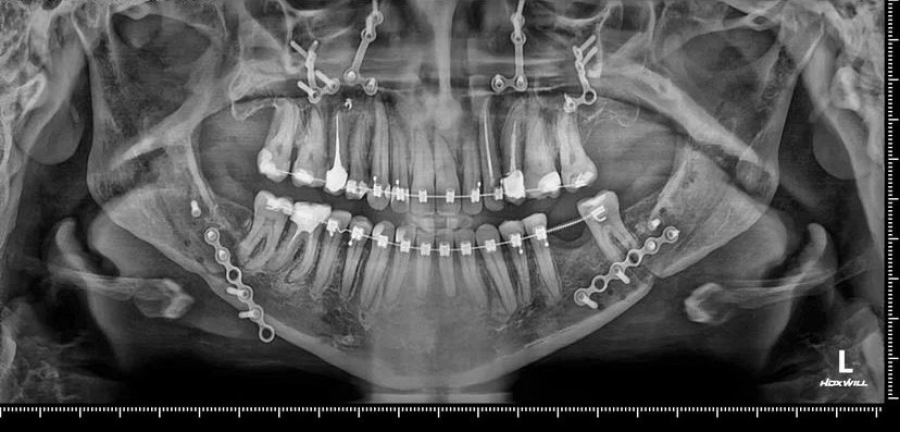

Специалисты городской клинической больницы №1 Волгограда провели первую серию сложнейших операций. Первой пациенткой челюстно-лицевых хирургов Романа Стасюка и Анастасии Мулиной стала  пациентка с гнатической формой зубочелюстной

аномалии, ей было показано проведение комбинированного ортодонтического и хирургического

лечения.

К специалистам пациентка обратилась с жалобами на неудовлетворенность эстетикой лица, нарушение функции жевания, недоразвитие верхней челюсти. После первого этапа лечения у врача ортодонта была достигнута

нормализация положения зубов, координация размеров зубных рядов. После клинического и

рентгенологического обследования, пациентка направлена в больницу для проведения двучелюстной остеотомии. Операция длилась более 6 часов

Уже через 4 месяца пациентке снята брекет-система и уже сейчас у пациентки нормализовалась функция жевания и улучшился внешний вид.